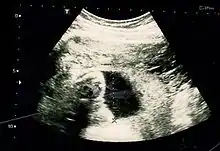

Fetus at 20 weeks

Fetal assessments

Obstetric ultrasonography is routinely used for dating the gestational age of a pregnancy from the size of the fetus, determine the number of fetuses and placentae, evaluate for an ectopic pregnancy and first trimester bleeding, the most accurate dating being in first trimester before the growth of the foetus has been significantly influenced by other factors.[24] Ultrasound is also used for detecting congenital anomalies (or other foetal anomalies) and determining the biophysical profiles (BPP), which are generally easier to detect in the second trimester when the foetal structures are larger and more developed.[25] Specialised ultrasound equipment can also evaluate the blood flow velocity in the umbilical cord, looking to detect a decrease/absence/reversal or diastolic blood flow in the umbilical artery.[26]

The safety of frequent ultrasound scanning has not been confirmed. Despite this, increasing numbers of women are choosing to have additional scans for no medical purpose, such as gender scans, 3D and 4D scans.[30] A normal gestation would reveal a gestational sac, yolk sac, and fetal pole.[31]

The gestational age can be assessed by evaluating the mean gestational sac diameter (MGD) before week 6, and the crown-rump length after week 6. Multiple gestation is evaluated by the number of placentae and amniotic sacs present.[32]